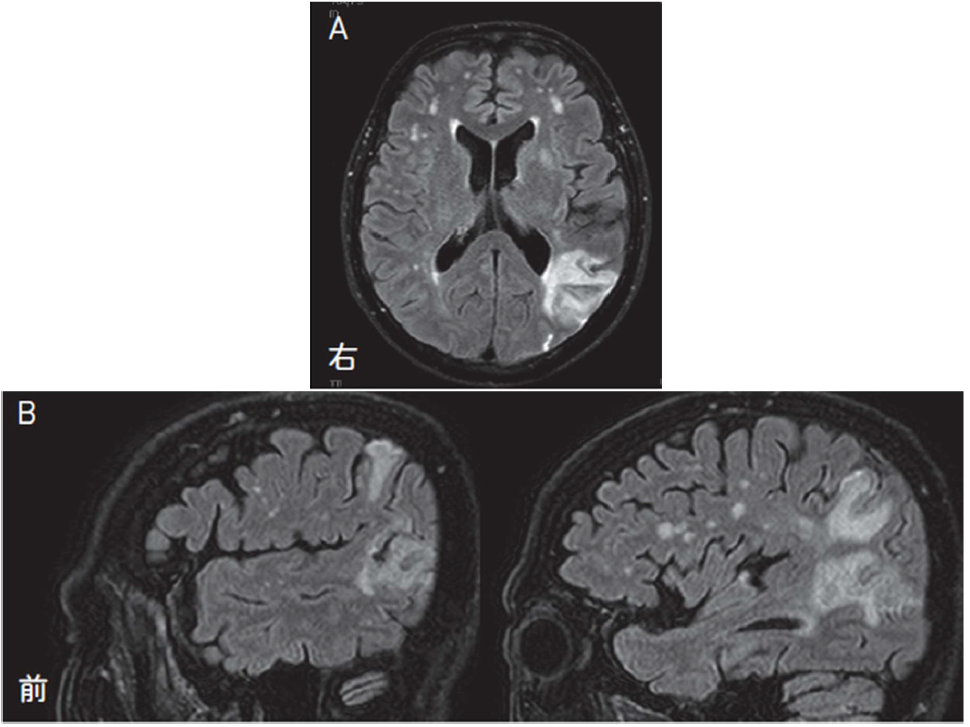

A:今日撮ったMRI では,FLAIR 画像で左頭頂葉に脳梗塞が確認されました(図5-3)。

K: 灌流画像で血流が低下していた領域だね。FLAIR 画像は少し時間が経って脳梗塞が完成すると高信号になるんだ。頭頂葉だけでなく後頭葉の外側面も高信号になっているのに気づいたかな。頭頂葉の梗塞部位をもう少し詳しくみると,頭頂葉下部の前方の縁上回,後方の角回が含まれているから,ちょうど観念運動性失行と観念性失行が出やすい部位だね。この前言ったように左角回はゲルストマン症候群と関係している部位だね。